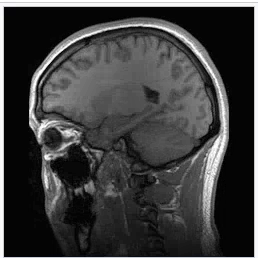

фото из открытых источников

Ядра атомов избирательно поглощают энергию электромагнитного поля, а затем возникает выделение энергии в виде радиосигнала, что и позволяет составить наглядный "фотографический" портрет исследуемого органа.